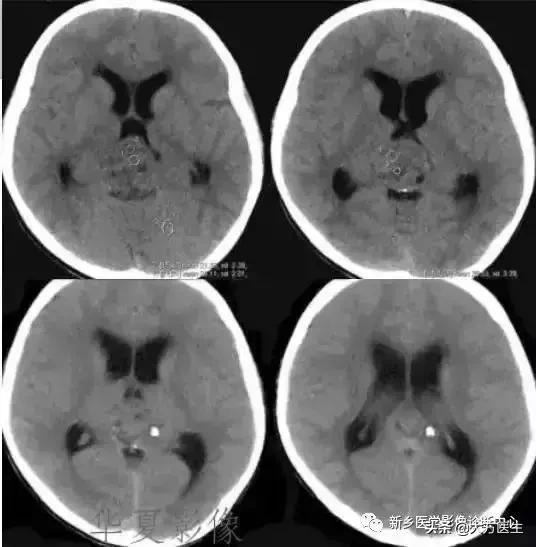

4、生殖细胞瘤

好发于10-20岁女性,松果体区及鞍上区多见。常有头痛、呕吐、视力减退等症状。

CT:颅内压增高症状及松果体区钙化。MR:常为脑三脑室后部长T1长T2信号,水肿不明显。增强明显强化。